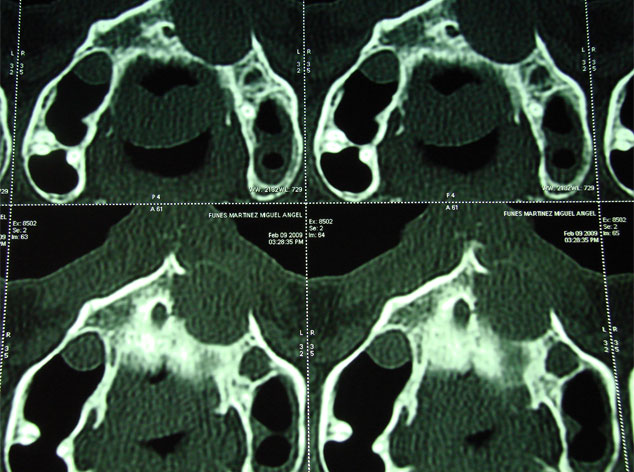

Para la reconstrucción, aconsejamos hacerlo en la misma intervención y con las bases de ingeniería tisular de la regeneración ósea guiada. Utilizamos como material óseo inductor el fosfato tricálcico tipo beta, mezclado con sangre del paciente y protegido con membrana de regeneración reabsorbible.